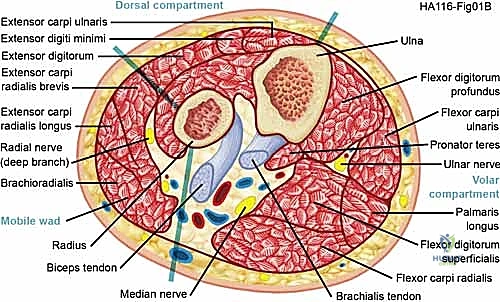

The forearm is anatomically dense and biomechanically complex, traditionally divided into three primary compartments, though clinical reality often dictates treating the superficial and deep volar compartments as functionally distinct entities during decompression.

The volar (flexor) compartment is the most frequently involved in ACS. It is subdivided into a superficial layer (pronator teres, flexor carpi radialis, palmaris longus, flexor carpi ulnaris) and a deep layer (flexor digitorum superficialis, flexor digitorum profundus, flexor pollicis longus). The median nerve travels between the FDS and FDP, making it highly vulnerable to ischemic compression. The ulnar nerve and artery course deep to the FCU.

The dorsal (extensor) compartment contains the superficial extensors (extensor digitorum communis, extensor digiti minimi, extensor carpi ulnaris) and the deep extensors (supinator, abductor pollicis longus, extensor pollicis brevis, extensor pollicis longus, extensor indicis). The mobile wad of Henry (brachioradialis, extensor carpi radialis longus, extensor carpi radialis brevis) is often considered a distinct lateral compartment. Decompression of the dorsal and mobile wad compartments requires vigilance to protect the superficial sensory branch of the radial nerve and the posterior interosseous nerve (PIN) as it dives beneath the arcade of Frohse.